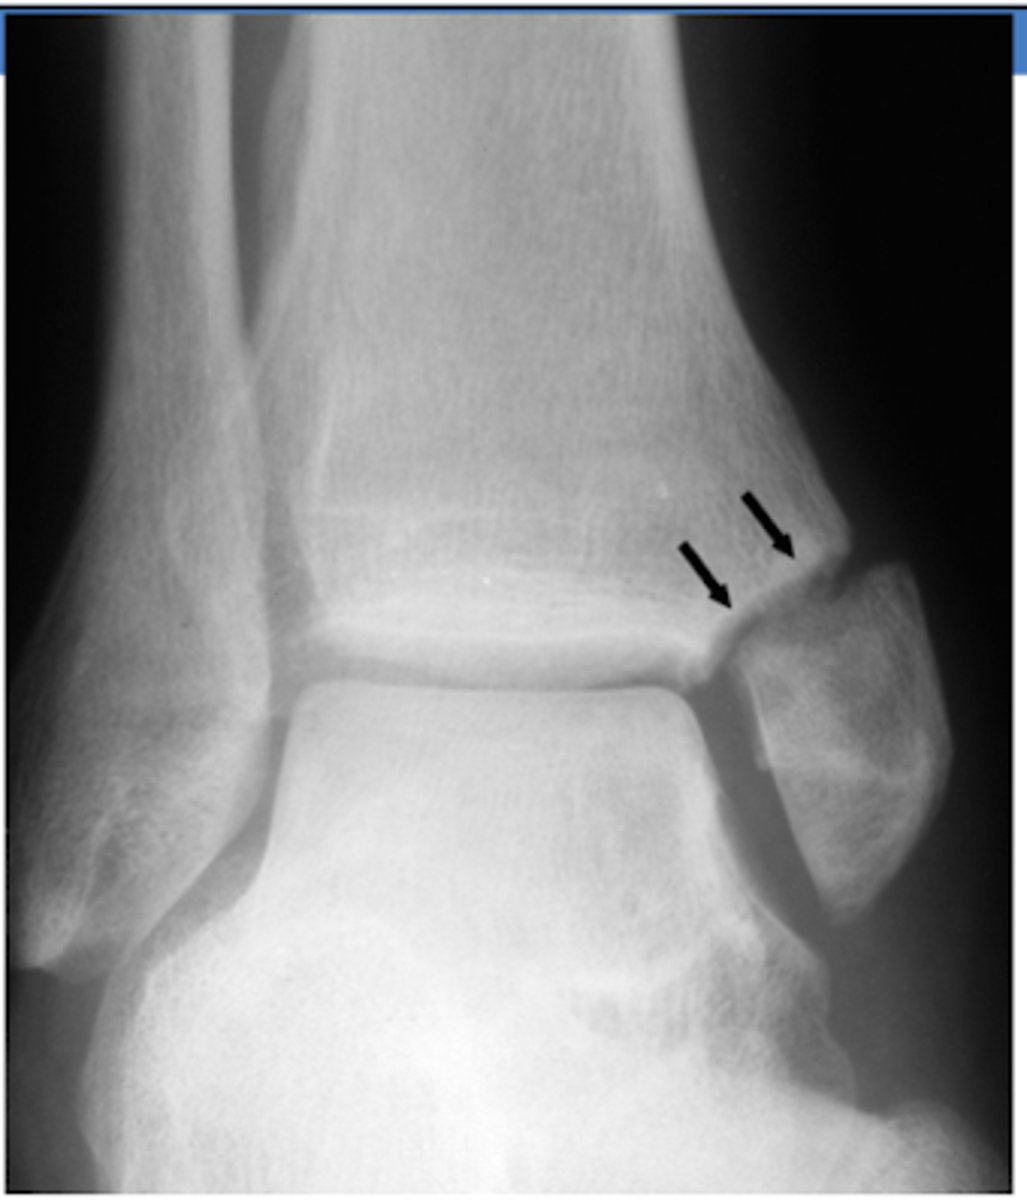

XR of Lateral Malleolus Fx with minimal displacement.